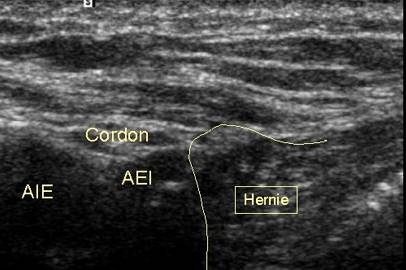

Deplasand sonda in sens caudo-cranial,

cordonul se deplaseaza

inafara si se plaseaza deasupra ostiumului arterei epigastrice inferioare

Herniile inghinale indirecte sunt mai frecvente (65% Ele corespund unui sac peritoneal care se exterioreaza prin foseta inghinala externa in afara vaselor epigastrice. Coletul herniar este in pozitie antero-laterala in raport cu ostiumul arterei epigastrice inferioare. Aceste hernii inghinale indirecte se intind mai mult sau mai putin in lungul cordonului pana la nivelul scrotului realizand o hernie inghino-scrotala